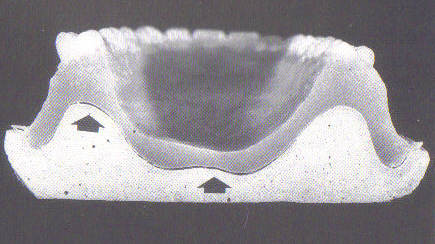

| Los flancos de la prótesis se han

retraído sobre las caras laterales de las tuberosidades y la base de

la prótesis se encuentra levantada con respecto al paladar. El

resultado es una falta de adaptación. Ver indicaciones de

flechas |